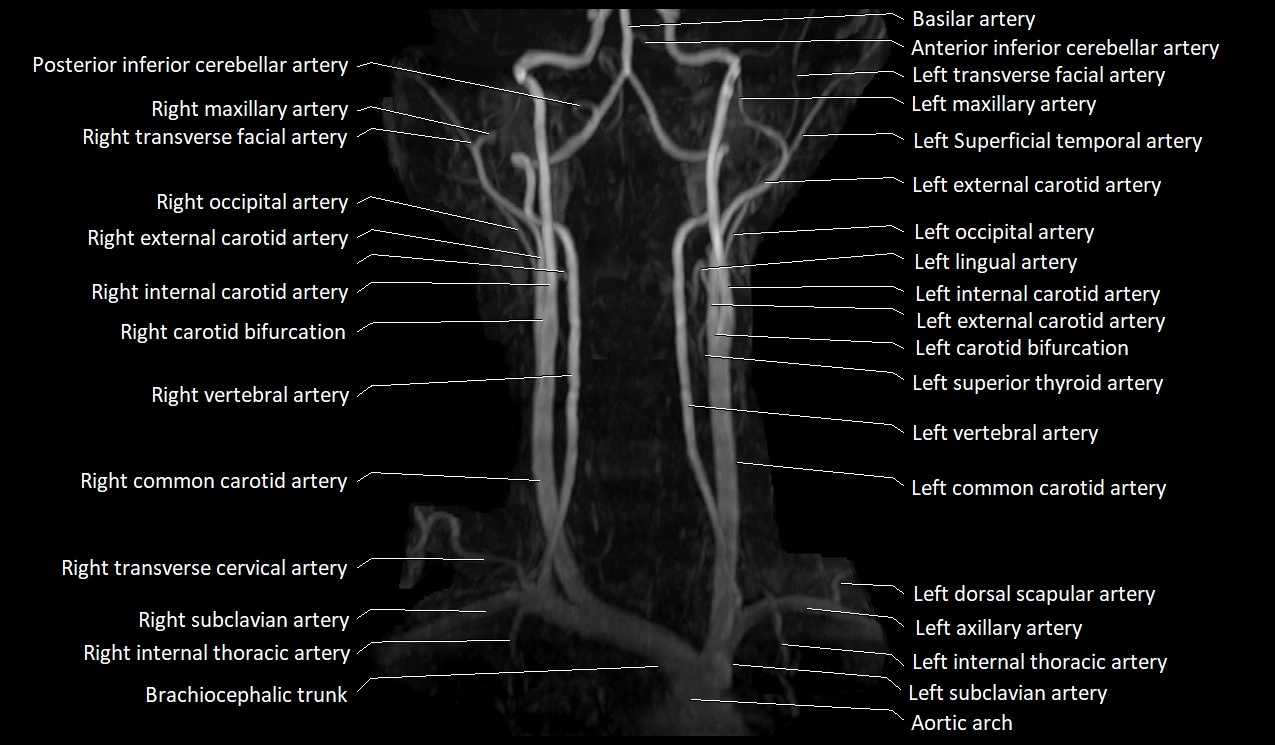

MRI images

image